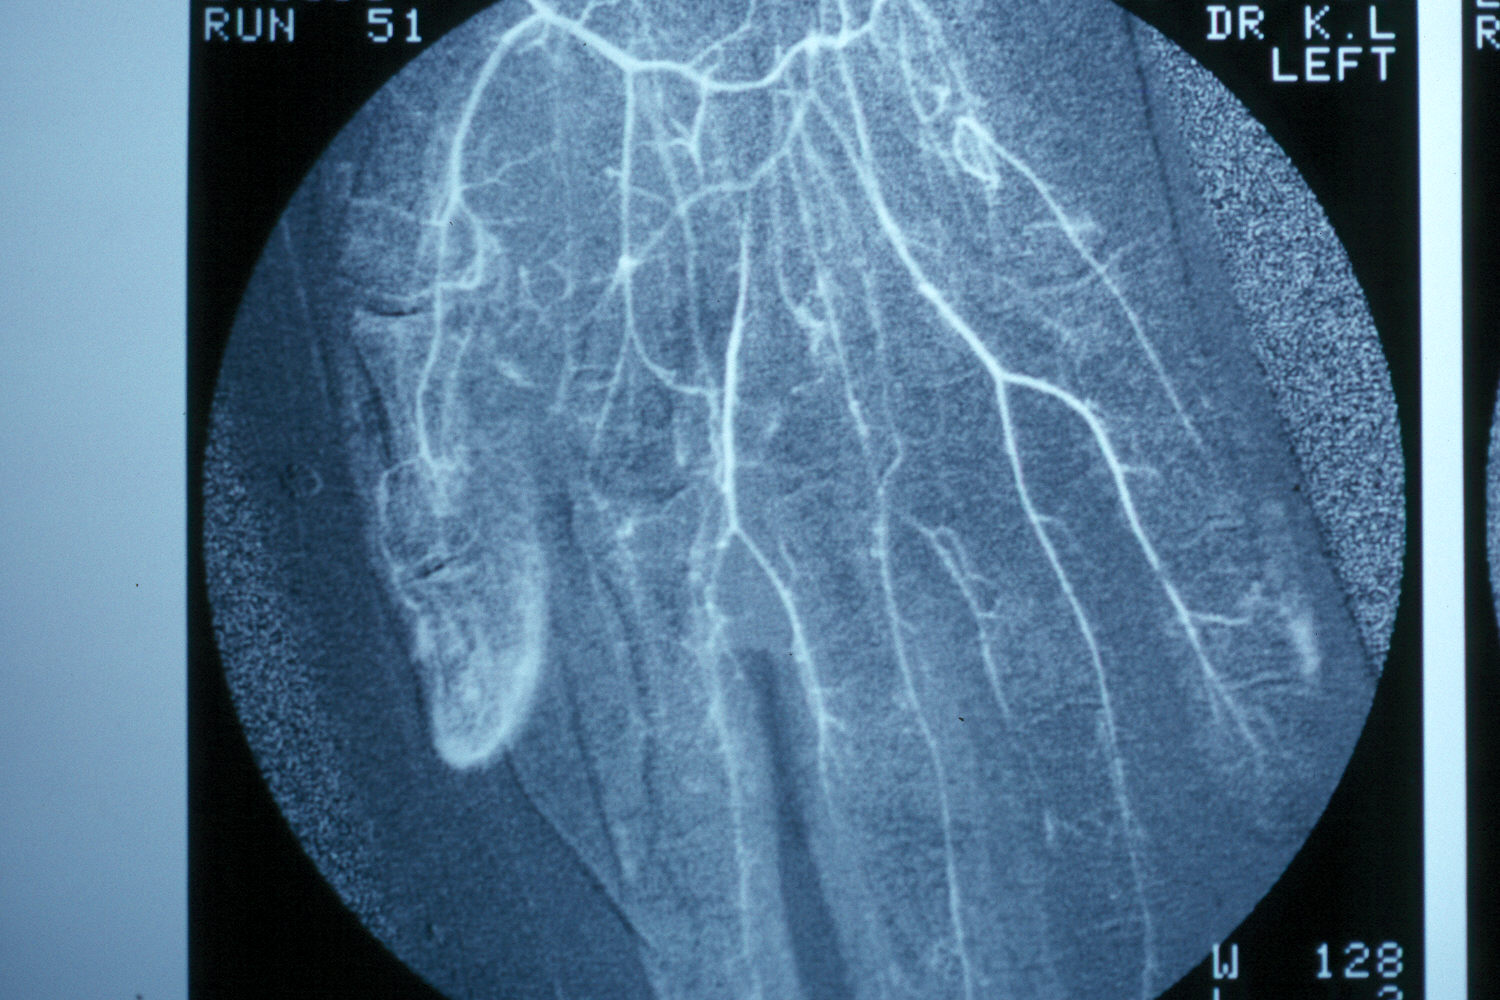

Arteriogram shows palmar arterial vessels to be patent, but diffusely narrowed.